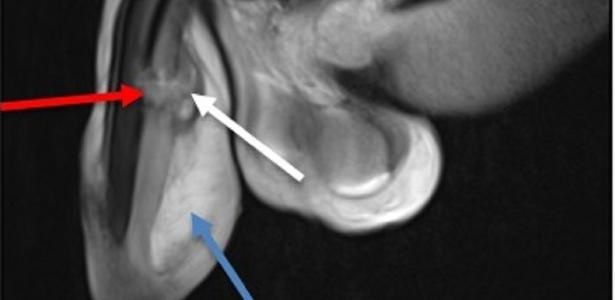

O paciente foi encaminhado para a ala cirúrgica de emergência, onde um urologista realizou o reparo da fratura peniana. Uma ultrassonografia revelou a presença de um hematoma nos corpos cavernosos do pênis, com maior intensidade no lado esquerdo. Por meio de ressonância magnética, os locais das lesões foram identificados.